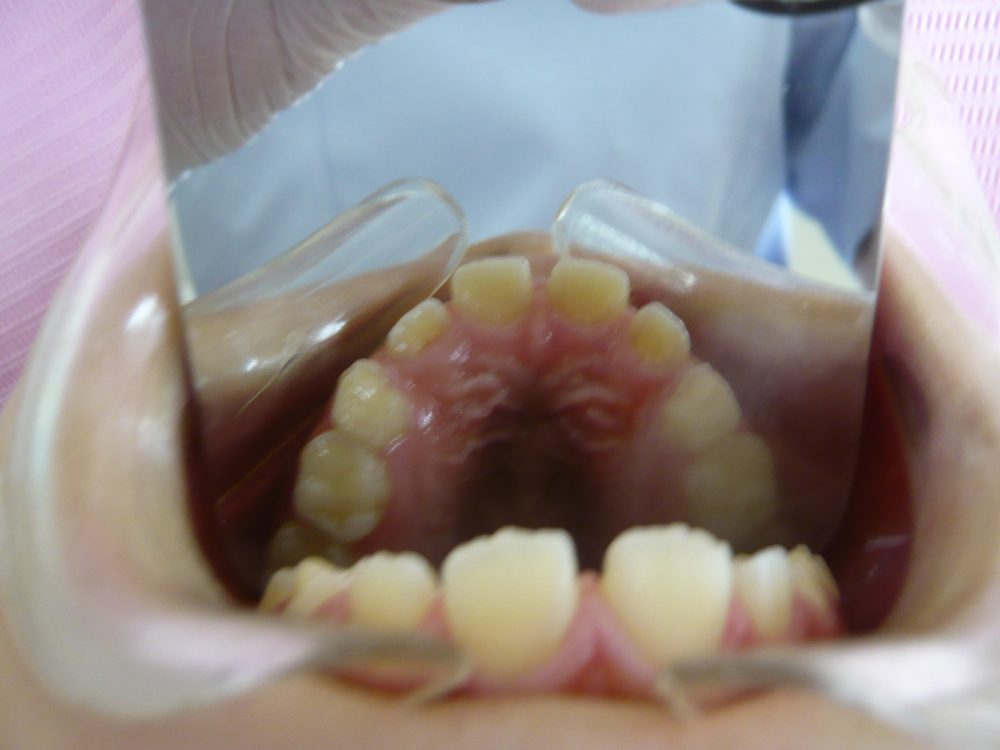

13歳 女の子 5年1か月

- 使用装置

- ブラケット、ワイヤー、マルチファミリー

8歳から矯正を開始、成長も関係するため、マルチファミリーという顎機能矯正装置も使いました。

また、治療中に上顎左右犬歯がかなり上から生えてきてしまったため、長期間の矯正治療となりました。

最終的にはとてもきれいになり、患者さんにもお母さんにも大変喜んでいただきました。